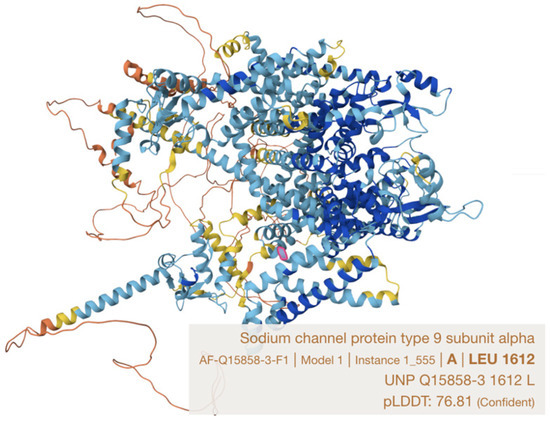

Here we describe a single case report with family history in a Han Chinese family harboring a novel likely pathogenic SCN9A variant (NM_001365536.1: c.4868T>A p.(Leu1623Gln)). This variant locates in a recognized hotspot for PEPD-causing mutations, the S4 in domain IV, which is close to the cytoplasmic linker between S4–S5 in domains III and IV, being a docking site for the inactivation gate (with IFMT motif) of the sodium channel [9,14] (Figure 3). This family represents the third genetically confirmed ethnic Chinese (Table 1) and the first local kin group showing atypical severe features of PEPD in two affected family members with similar disease trajectory, characterized by carbamazepine refractoriness, requirement of intensive pain control, progressive worsening from childhood to late adulthood and potentially life-threatening psychiatric impact.

Figure 3.

Leucine 1623 residue in Nav1.7 protein (Q15858-1), which is equivalent to leucine 1612 on Q15858-3 protein (marked in pink) (model constructed by AlphaFold).